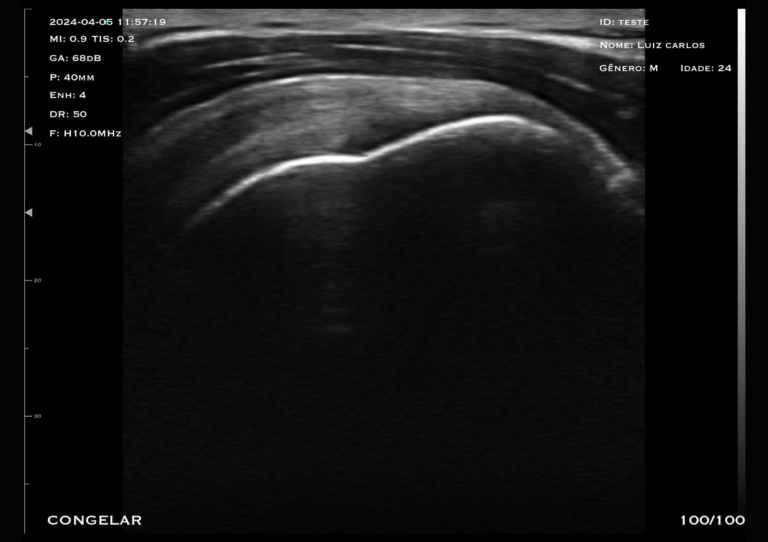

Com apenas 240g, sem fio, e com longa duração de bateria, o Mobissom/Clarius é o menor e mais completo ultrassom ultra portátil do mercado.

Altíssima definição de imagem e liberdade para realizar exames em qualquer lugar do mundo!

Conecte-se via Wi-Fi com seu dispositivo móvel e visualize as imagens através de um aplicativo diretamente na tela do seu celular ou tablet.

Desde 2016, somos os pioneiros na tecnologia dos ultra portáteis

Presente em todo o território nacional com base instalada de +5000 equipamentos.

100% regularizada com registro na Anvisa, Inmetro e Anatel.